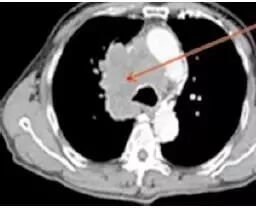

癌,乃魔鬼,张牙舞爪的魔鬼,甚至是吸血鬼。所以,肺癌的CT的特征就是不规则的肿块,有毛刺、分叶,牵拉胸膜引起胸膜凹陷,烂糟糟的空洞,吸血鬼征:血管向肿块聚拢,以供肿瘤吸血。

这么多征象一起存在,肺癌妥妥的,接近100%。

典型肺癌。

看吧,肺癌就是不规矩。

看吧,肺癌就是乱七八糟。

肺癌:吸血鬼特征。